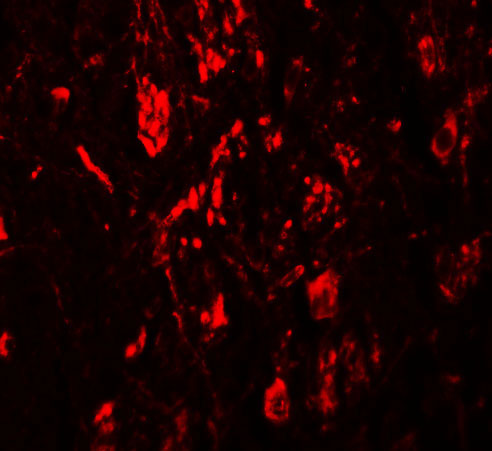

| Application Notes | LRRTM4 antibody can be used for detection of LRRTM4 by Western blot at 1 µg/mL. Antibody can also be used for immunohistochemistry starting at 2.5 µg/mL. For immunofluorescence start at 20 µg/mL. |